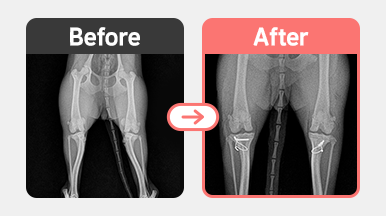

[슬개골 탈구 수술] 비숑 / 2살 / 양측 MPL (우 G3 / 좌 G2)

2025-11-21